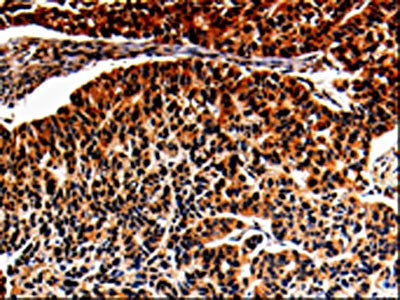

IHC (Immunohistochemistry)

(The image is immunohistochemistry of paraffin-embedded Human lung cancer tissue using AAA237029(ALOX5 Antibody) at dilution 1/25. (Original magnification: ×200))